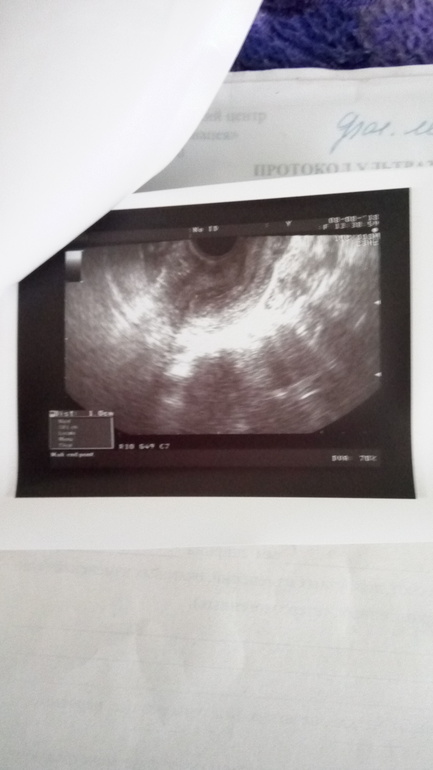

Фолликулометрия

На сегодняшний день вот такая картина 15 ДЦ,сейчас будем ставить укол,правда тревожит что опять в левом,но врач сказала что эндометрий хороший можно уколоть укол,буду надеяться что получится😳